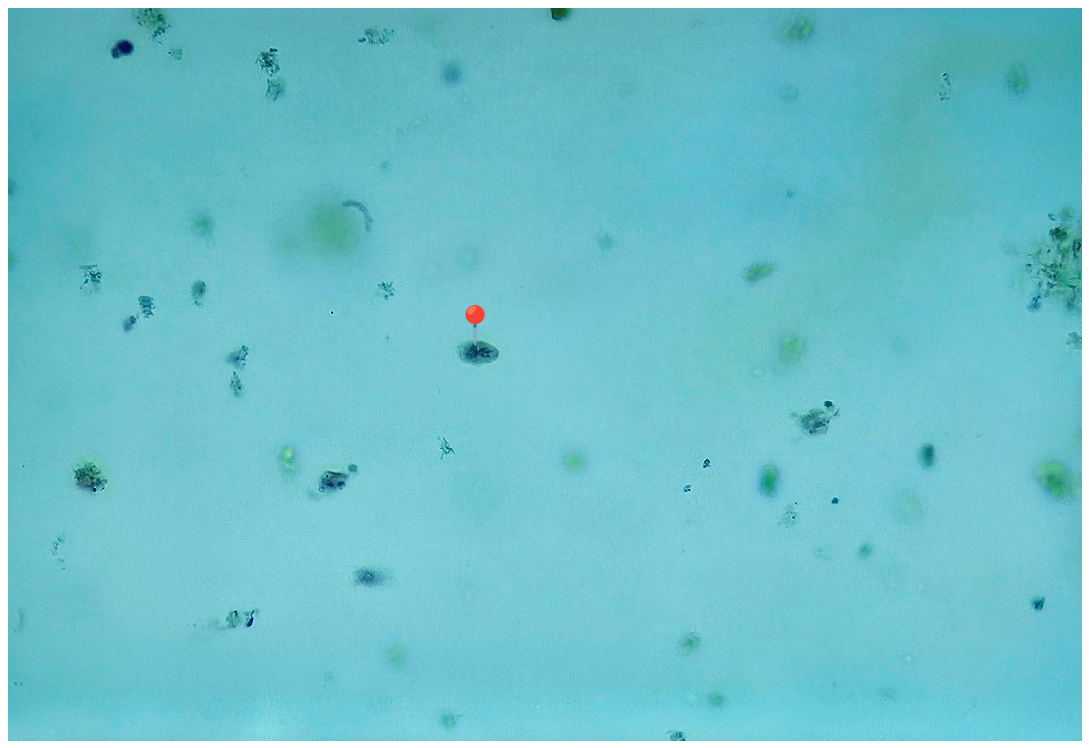

🩸🤖 Plasmodium sp. (śledziona - malaria melanemia)

🧩🦠 Cechy charakterystyczne:

🔴🟡🟢️🟤 - złogi hemosyderyny.

😷❓ Parazytoza: Malaria